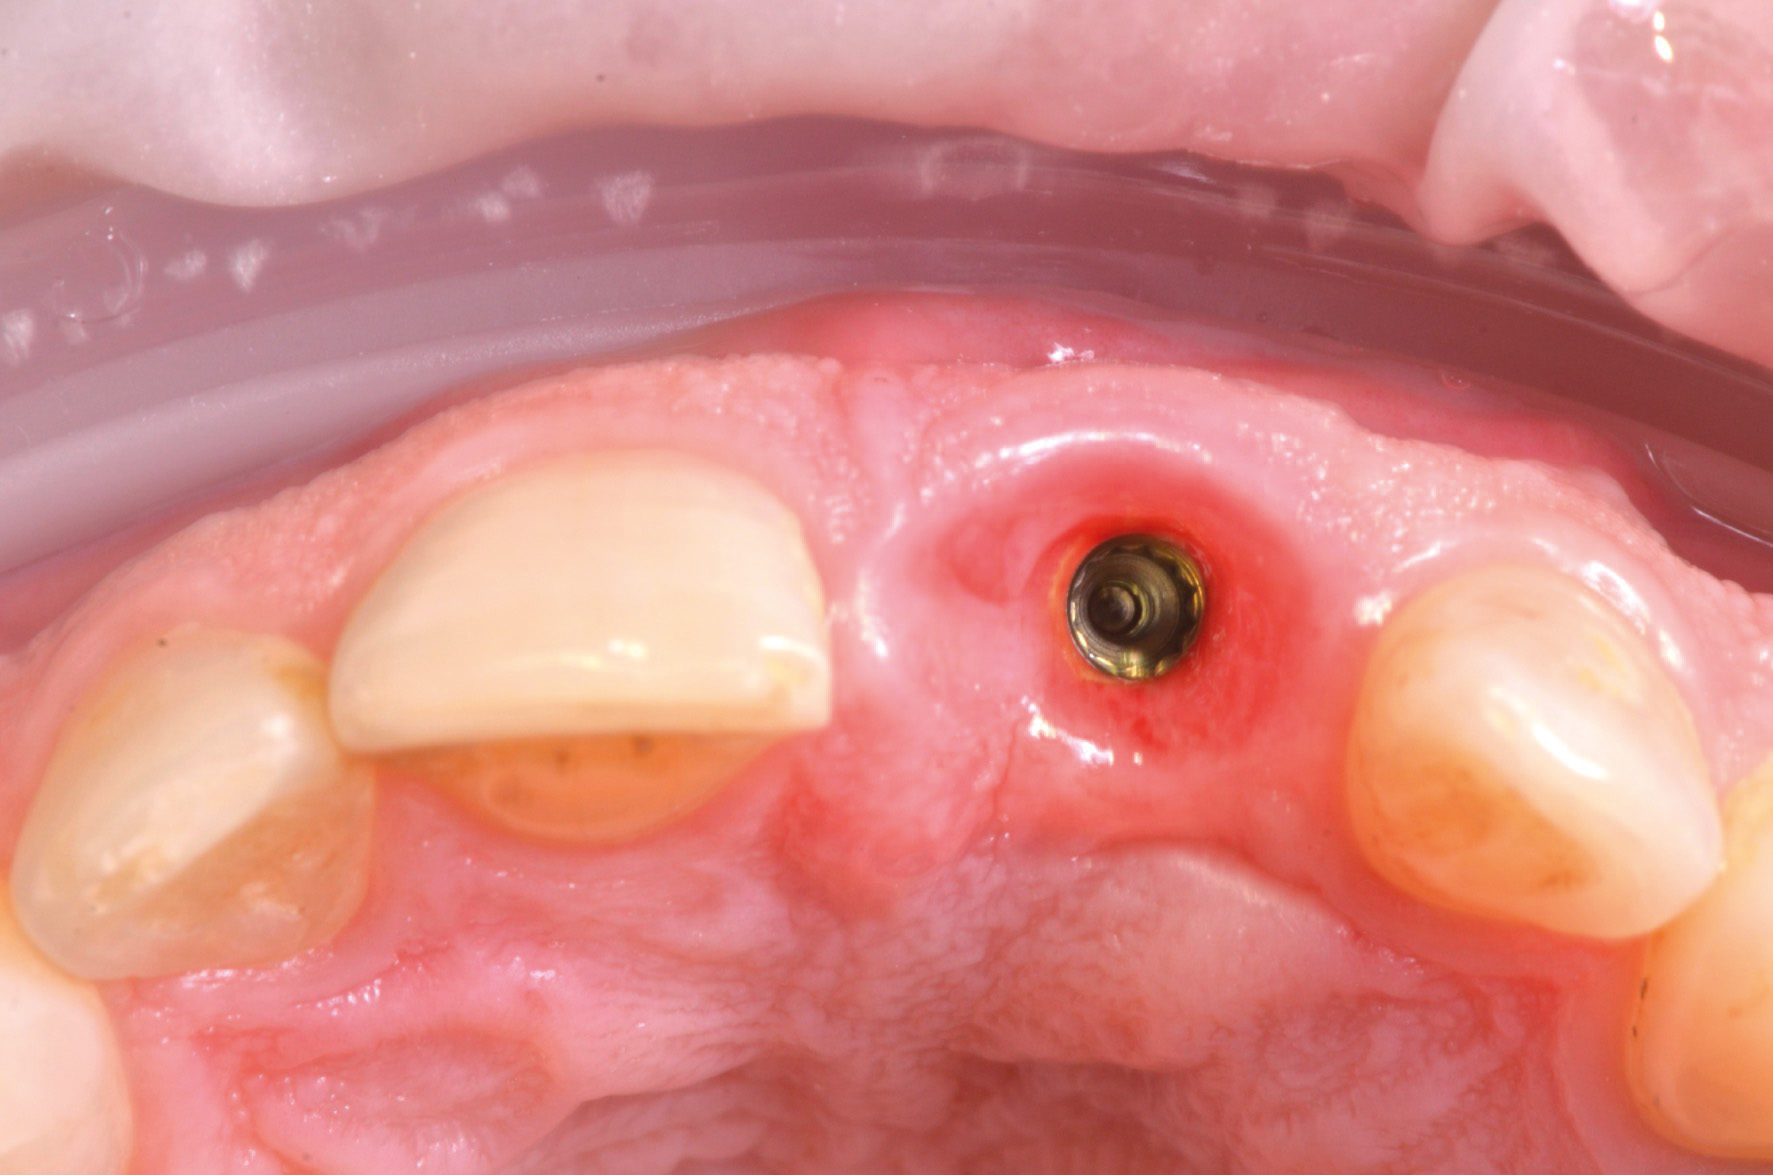

Previa somministrazione di anestesia plessica, l’elemento 2.1 è stato estratto con una procedura minimamente invasiva senza sollevare lembi (fig.6).

Una volta posizionata la dima chirurgica si è eseguita l’osteotomia guidata con frese a diametro crescente ed è stato posizionato l’impianto (MIS V3, MIS Implants ltd global, Bar Lev, Israele)(fig.7,8).

Seguendo le indicazioni del progetto chirurgico/protesico è stato posizionato un pilastro intermedio in titanio anodizzato (MIS Connect, MIS Implants ltd global, Bar Lev, Israele) con la tecnica del “one-abutment-one-time” con lo scopo di spiazzare la connessione protesica in una posizione più coronale (fig.9).